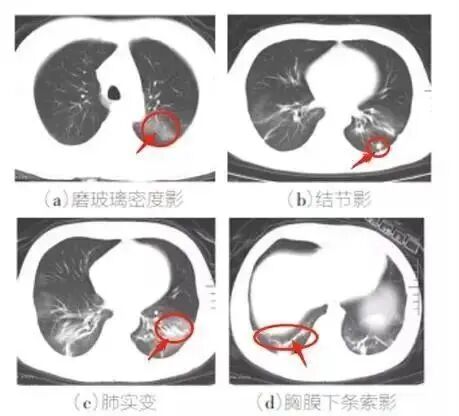

2、胸部CT特征:多發磨玻璃影、斑片影及實變影

新冠病毒無癥狀感染者指呼吸道等標本新型冠狀病毒病原學檢測呈陽性,無相關臨床表現,如發熱、干咳、咽痛等可自我感知或可臨床識別的癥狀與體征,且CT影像學無新冠肺炎影像學特征者。